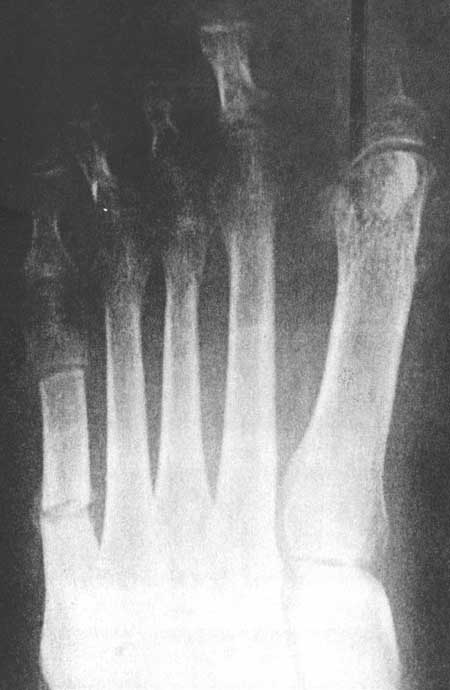

Fig 3B (pre-operative)

|

Fig 3B (post-operative)